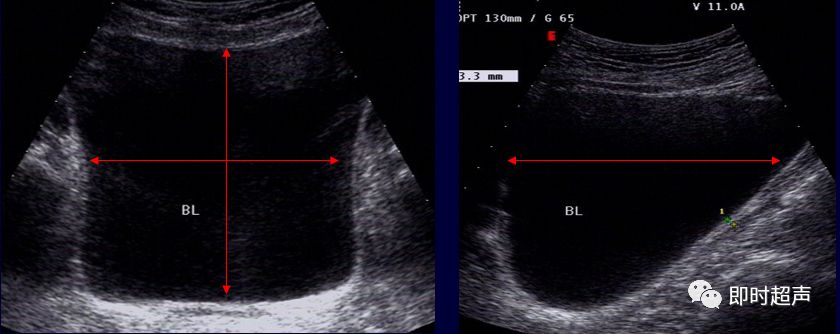

膀胱正常结构超声图像特点:适度充盈的膀胱在声像图中是一个囊状结构

图片尺寸620x401